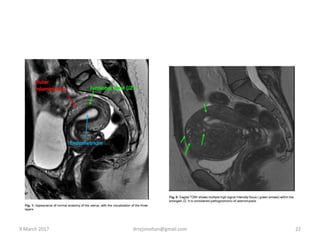

MRI

โ€ข The JZ is well demonstrated on T2-weighted MRI

images

โ€ข Features predictive are JZ >12mm and

hemorrhagic high signal myometrial spots.

Three objective parameters for diagnosing AM

on MRI

1.Thickening of JZ>=12mm

2.A ratio of max thickness of the JZ/total

maximum myometrialthickness >40%

3.A difference between JZ max and JZ min

>5mm- most trust worthy criteria

Sagittal T2-weighted MR image shows diffuse, even thickening

of the junctional zone (arrows), a finding consistent with

diffuse adenomyosis